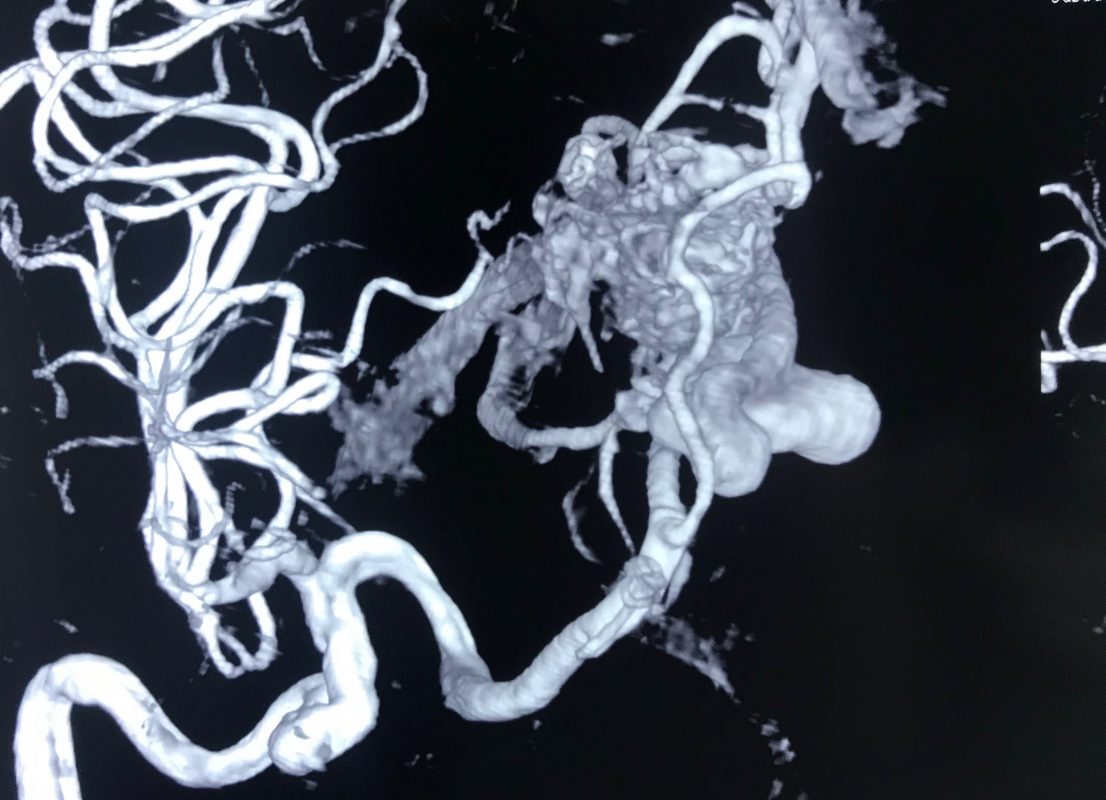

奇形動脈は太く拡張しており、血液循環が速いため、脳出血を起こすことがよくあります。

血液を排出する静脈も AVM プロセスによって拡張 (静脈瘤の出現) を受ける可能性があり、症例の 15% で動脈瘤が形成されます。どちらも脳出血を引き起こす可能性があります。